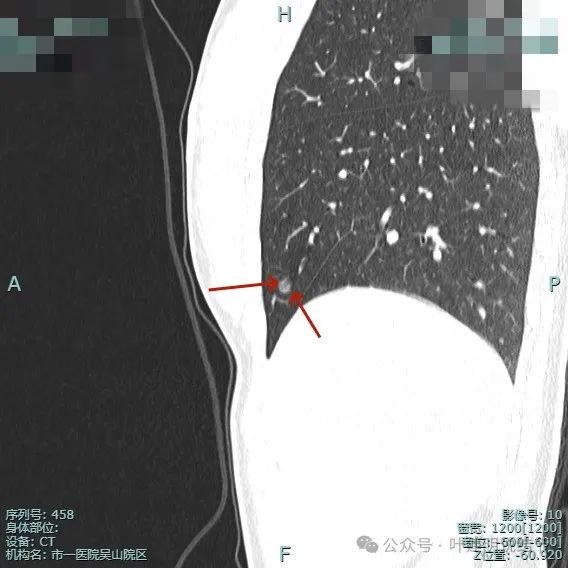

各病灶的影像特征以及考虑如前述。我们最要关注的左侧是病灶10,右侧是病灶15。主要是由于这两处密度不纯,风险相对较大。两侧相比,左侧病灶10(以下称病灶A)由于紧贴叶间裂,有点状高密度,表面毛刺与多支微小血管进入,风险更要大于右侧病灶15(以下称病灶C)。所以需要处理的话,应该先处理左侧。那么左侧的病灶共有7处,是否有性格“一网打尽”式解决左侧7处病灶呢?由于病灶分散在上叶与下叶不同部位,有的位置还靠中间些,如果均外科解决所有病灶显然就算勉强切掉,也是左侧肺受损严重,关键是我一直强调的“由于致病因素未知,解决了目前已经发现的多发病灶,并无法预防后续再检出结节,而本就已经多达10几处的话,后续再检出新的是必然的,否则逻辑上解释不通”。当然病灶2(以下称病灶B)由于也是靠胸膜很近,而且在左侧的7处病灶中,它的风险与大小排在第2位,如果术中能从胸膜表面发现异常,能楔形切除,那该考虑一并切了。若发现不了,则只处理病灶A也是能接受的。至于右侧,早在十几年前我们自己也主要双侧同时手术,但那时认识不够,现在知道多发的很常见,也解决不了后续再长的问题,那么风险较小的一侧当然可以先缓缓,等以后有进展并风险增加时再考虑干预处理。所以右侧的病灶C虽然也有一定风险,但处理与否则要排在后面考虑。

杭州市第一人民医院胸外科叶建明团队为其进行了单孔胸腔镜下左肺部分切除术。术中发现病灶B也已在肺表面看出异常,遂予以局部楔形切除,病灶A当然能从叶间裂处直接看到,也予以切除。